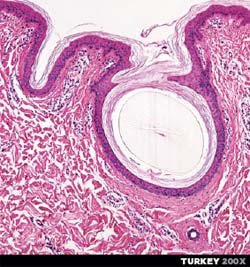

Turkey looks like a stun double for the Blob...